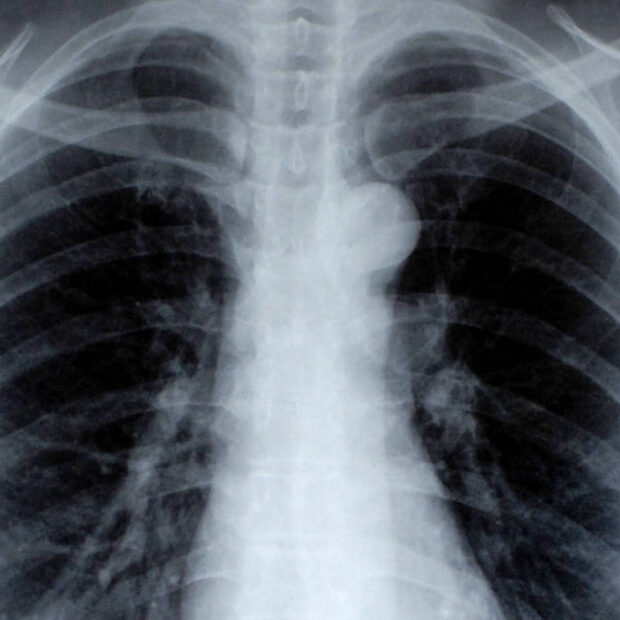

Em uma nova pesquisa, cientistas da Bélgica descobriram que a disponibilidade do aminoácido aspartato no pulmão pode ser uma das razões para mais da metade dos pacientes com câncer e metástase terem esses órgãos afetados pelas células cancerígenas.

Cada tipo de tumor gera metástases com preferências por determinados órgãos. Muitos deles pelo pulmão, como no caso dos cânceres de mama, rim, esôfago ou mesmo de outro pulmão. O osso e o cérebro também estão entre os alvos mais comuns.

O aspartato é uma das peças usadas na formação das proteínas (chamadas aminoácidos), normalmente encontrado em baixas concentrações no sangue. Entretanto, em pacientes de metástase, está presente em grandes quantidades nos pulmões. Os especialistas belgas foram capazes de identificar com precisão o mecanismo pelo qual essa pequena molécula é capaz de deturpar o funcionamento normal do organismo.